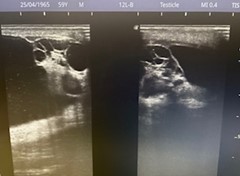

Estudio ecográfico testicular muy accesible sin preparación:

Caso 1: Aumento del volumen escrotal a expensas de la ocupación del hemiescroto izquierdo por grasa mesentérica, sin implicación de asas a través de la OII del canal inguinal (hernia inguinoescrotal izquierda indirecta)